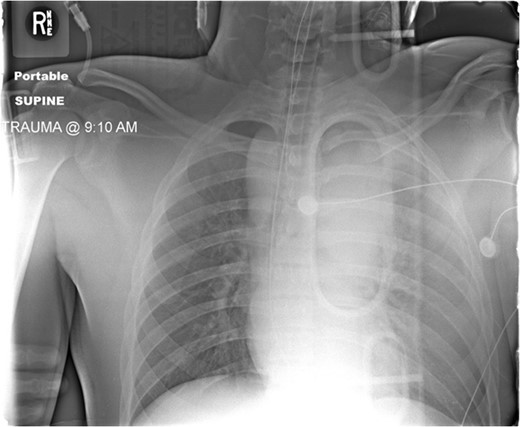

Admission AP CXR demonstrating a widened mediastinum and increased haziness of the left hemi-thorax.

During the abdominal exploration, multiple mesenteric injuries were identified and repaired. An abbreviated damage control laparotomy with packing was performed. A left-sided chest tube was inserted and drained ~800 ml of blood without continued hemorrhage.